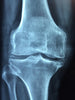

Joints are the connections between bones, providing support and facilitating movement. Cartilage, synovial fluid, and surrounding muscles and ligaments play crucial roles in joint function. Over time, wear and tear, inflammation, and injury can affect joint health, leading to conditions like osteoarthritis and rheumatoid arthritis.